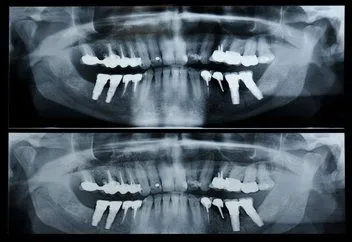

Panorex

A panorex is a very impressive piece of imaging machinery in that it is capable of identifying many issues and structures that a normal x-ray is not. Initially you will sit in a chair with your chin on a small ledge. Once positioned in the machine, it will rotate around your entire head taking a full 360 degree view of the teeth, head, sinuses and bones.

The ability to view the full structure of your head as a whole is very informative to the dentist. It will allow us to see any potential problems and make sure that everything is functioning as it should be. The panorex is capable of viewing specific types of structural problems, infections or asymmetry among many others.